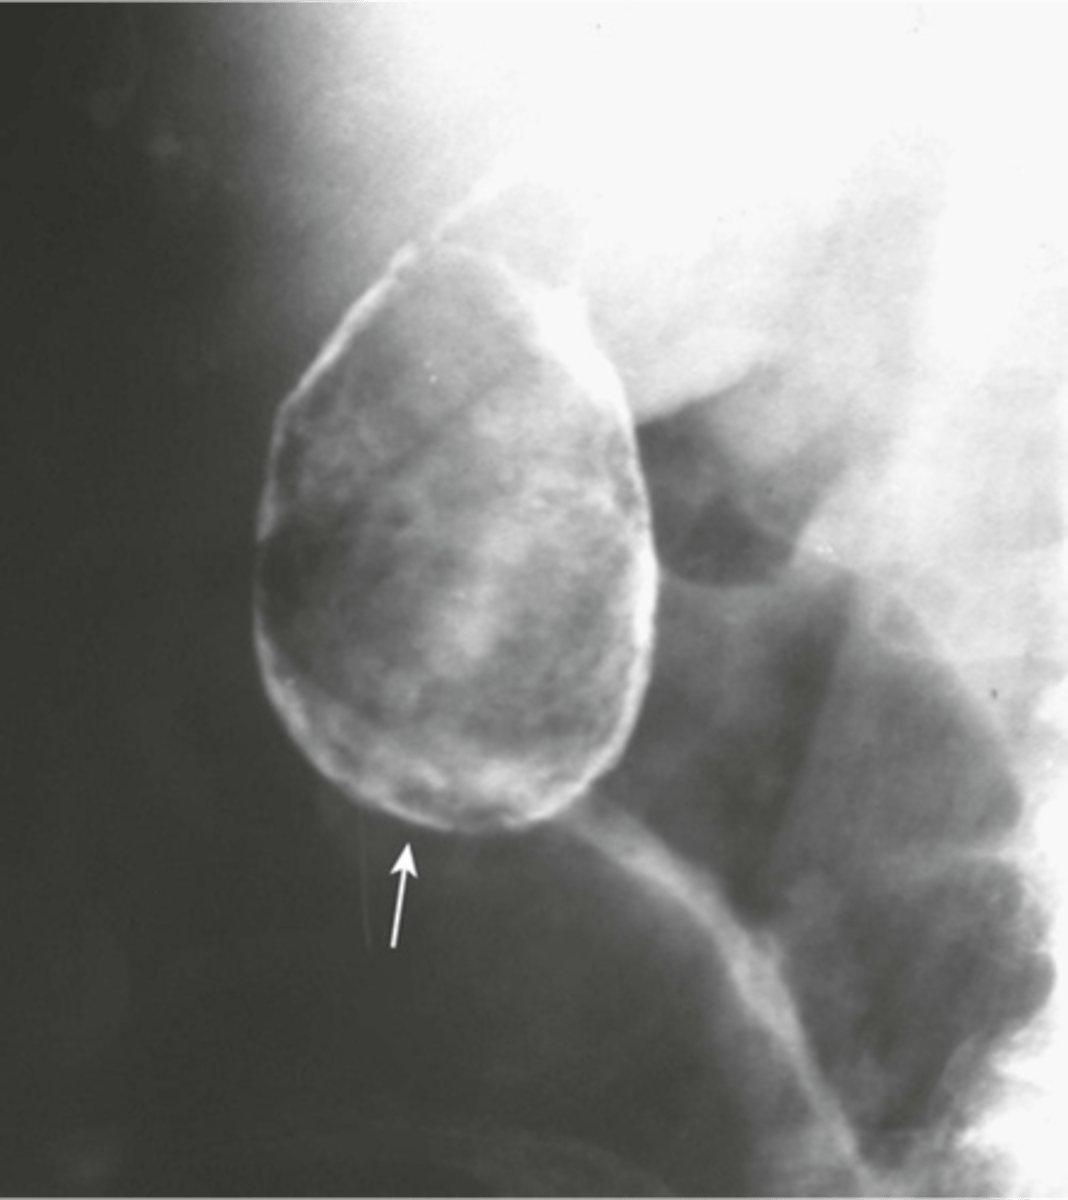

Phleboliths (venous calcifications)